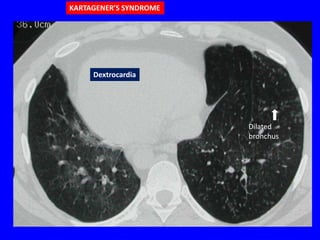

IMMOTILE CILIA SYNDROME

• Diffuse bronchiectasis

• May have situs inversus (Kartagener’s

syndrome

Bronchiectasis

Dextrocardia

KARTAGENER’S SYNDROME

Dilated

bronchus